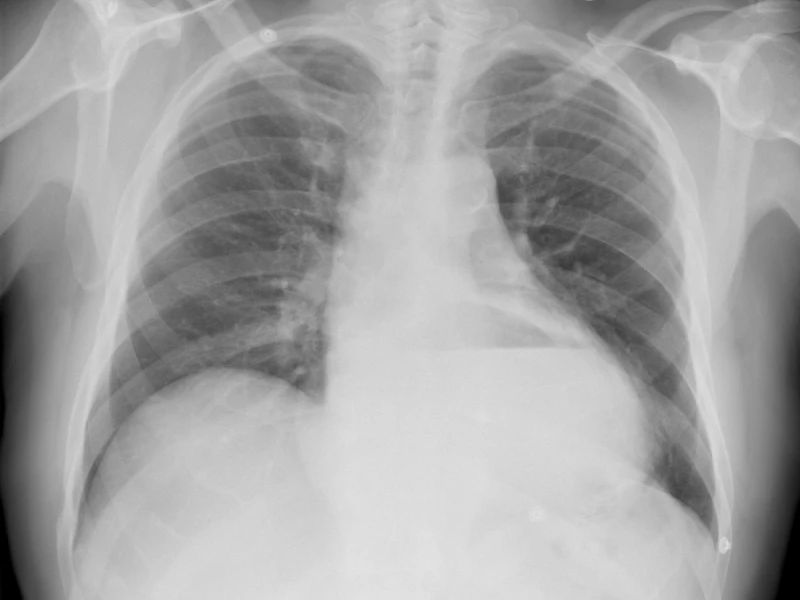

Radiografía de tórax

- ABCDEF — Post de mnemotecnia (publicado): “Informe de la radiografía de tórax: Mnemotecnia ABCDEF”.

- Guía aplicada (publicada): “Cómo interpretar una radiografía de tórax”.